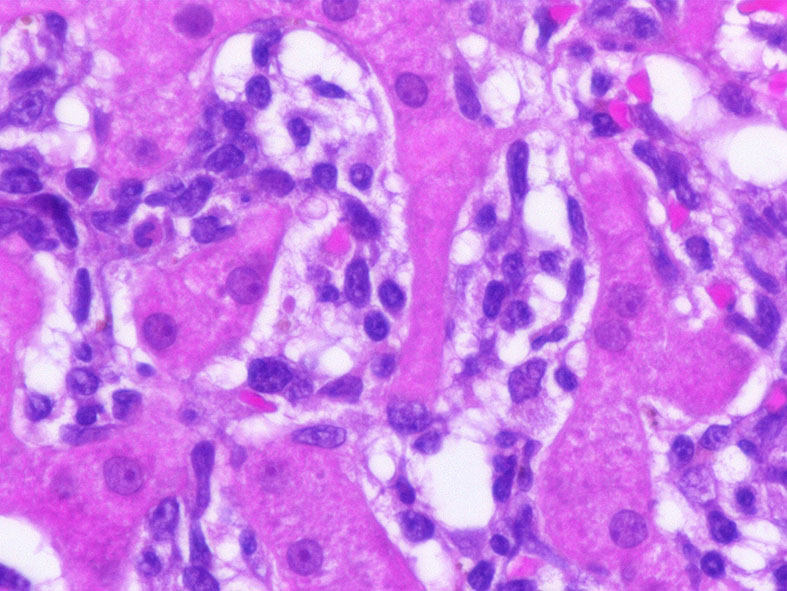

類洞内に浸潤増殖するリンパ腫細胞: 類円形・長円, 瓜状の核をもつ,細胞質の乏しい細胞(サムネイル画像のクリックで大きな画像が見られます)

類洞内で増殖する腫瘍細胞はCD3+, CD7+のT-cellであるがCD5発現が弱く, 異常なT-cellである.

CD4は類洞内皮/macrophageの一部が陽性であるが, 類洞内腫瘍細胞の多くは陰性を示す(陽性と間違えないこと). CD8陰性. CD20陽性リンパ球はごく少ない.